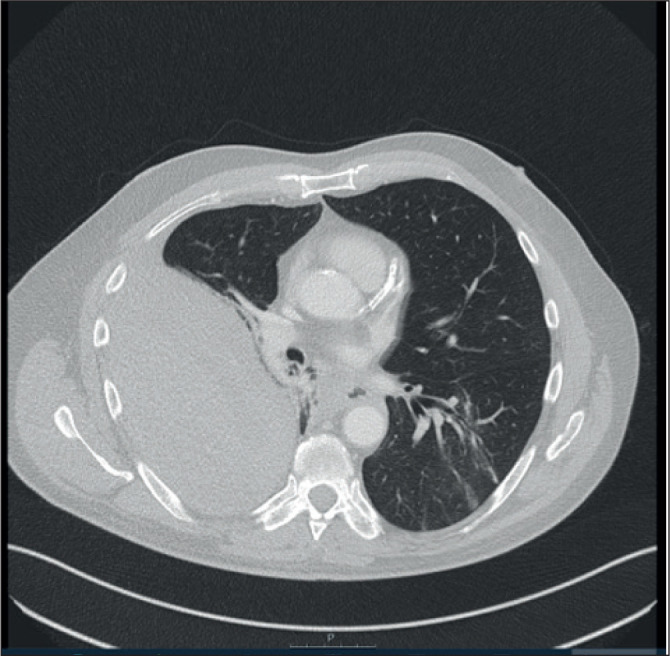

Extrapleural Haematoma following Percutaneous Coronary Intervention.

Abstract Image